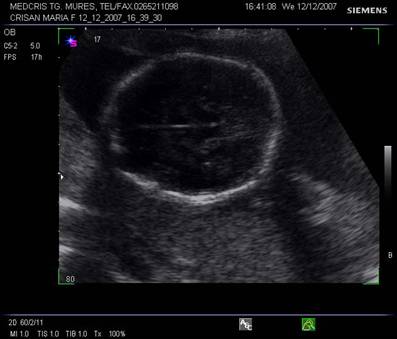

Planul III sau planul frontooccipital, pentru masurarea diametrelor biparietal si frontoocipital. Ecoul de mijloc frontoocipital este intrerupt in zona cavum septum pellucidi, anecogena, situata anterior de ventriculul III. Acesta este situat intre doi nuclei talamici hipoecogeni si apare ca o despicatura mica sau o linie.

Fig. nr. 151 Planul III de sectiune transversala a craniului fetal.